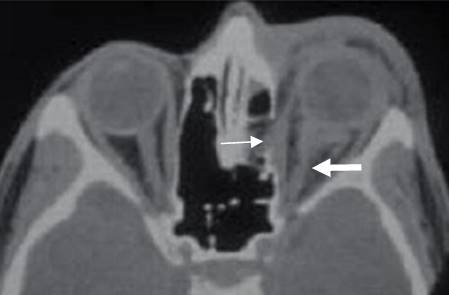

Fig 215 C. Fractura de órbita.

A: TAC axial y B: TAC reconstrucción coronal. Fractura en el borde interno de la órbita.

C: TAC axial en ventana de tejidos. Hay herniación de la grasa, pero permanece intacto el músculo recto interno.